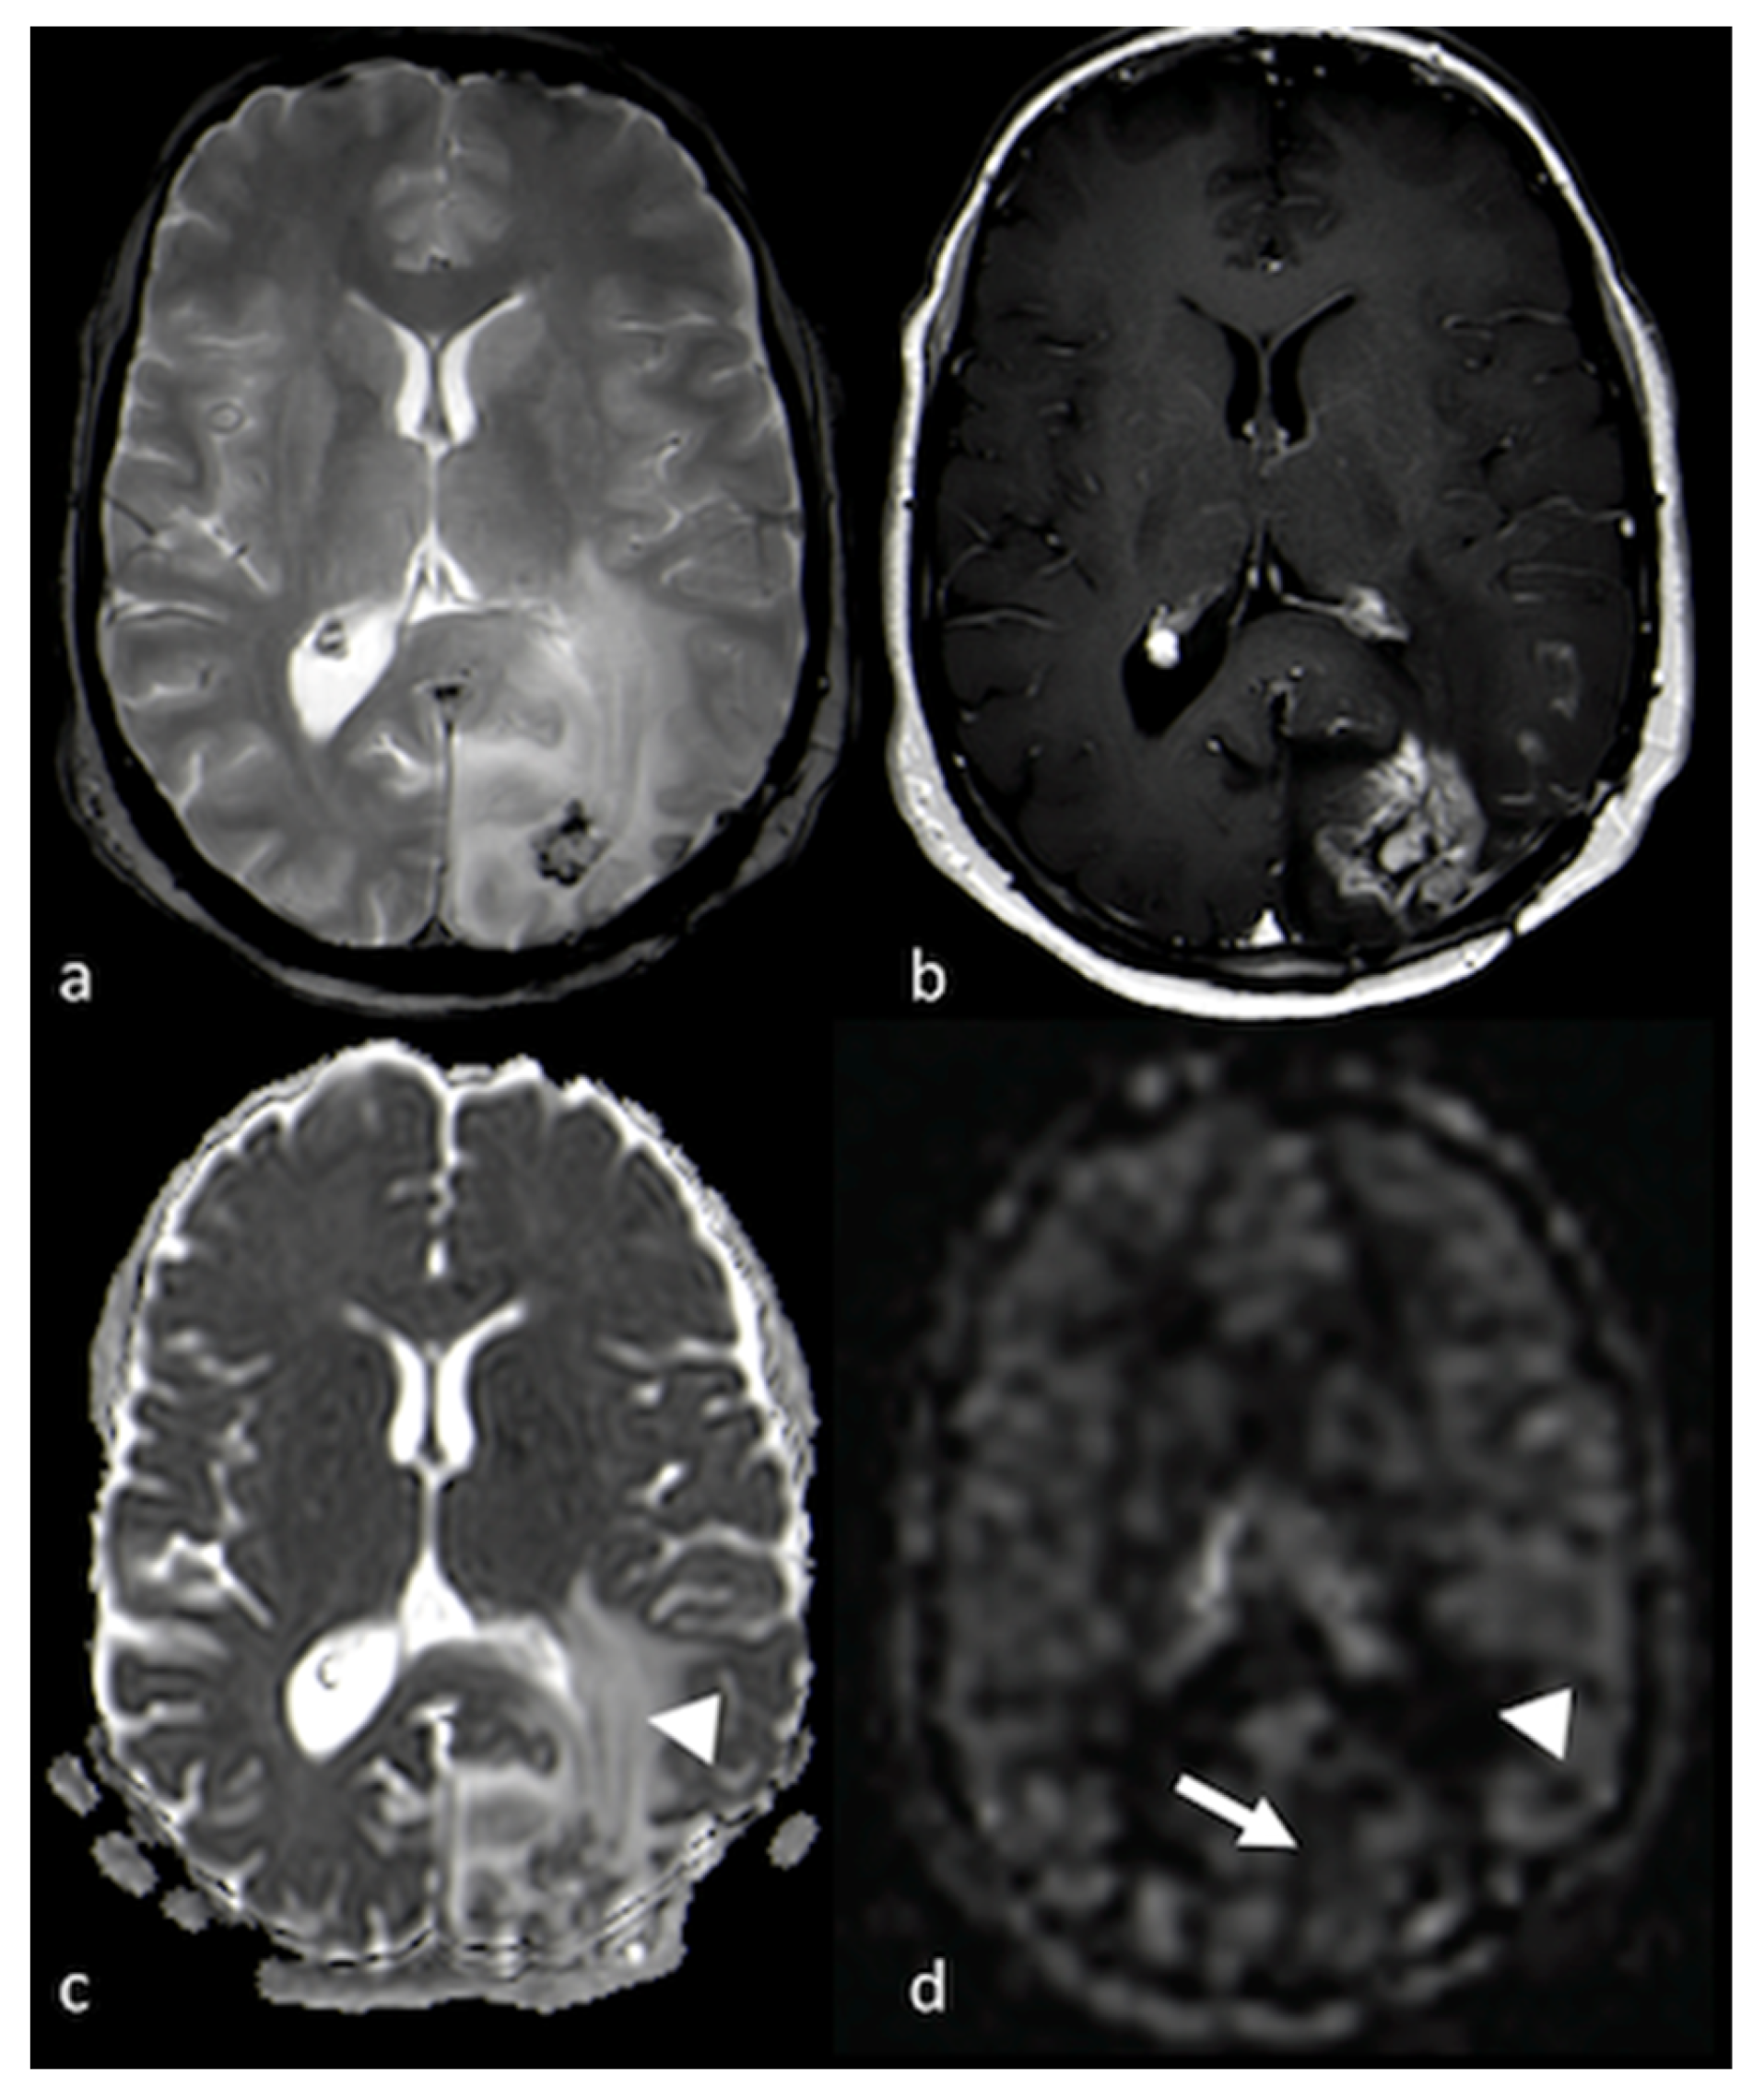

3.2.1. Diffusion-Weighted Imaging (DWI)

- Lee, E.J.; terBrugge, K.; Mikulis, D.; Choi, D.S.; Bae, J.M.; Lee, S.K.; Moon, S.Y. Diagnostic value of peritumoral minimum apparent diffusion coefficient for differentiation of glioblastoma multiforme from solitary metastatic lesions. AJR Am. J. Roentgenol. 2011, 196, 71–76. [Google Scholar] [CrossRef] [PubMed]